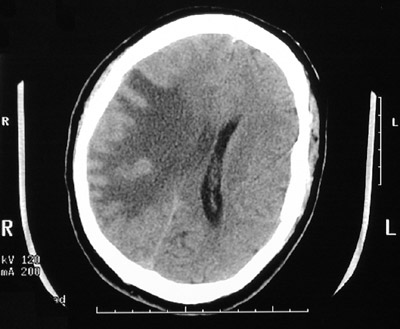

| The CT scan views of the head above and below demonstrate areas of low attenuation representing marked vasogenic edema adjacent to an area of tuberculous meningitis and tuberculoma formation in a patient with disseminated tuberculosis. Note the effacement of the lateral ventricles on the left and the shift of the midline. |